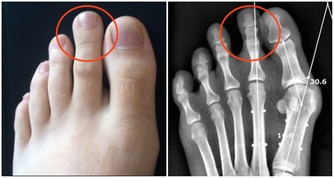

*****1、肢體發麻*****

如果起床時發現肢體有麻木感,不要認為是小毛病。肢體發麻是很多慢性疾病會發出的信號,例如高血壓、糖尿病、高血脂症,這些類型的疾病在發展過程中指標不正常,無形中會影響血管,神經功能,如果局部的循環出現障礙,肢體需要的營養物質,血液無法及時提供,會出現不良症狀,其中較常見的特徵是肢體麻木。

發現以上信號需要及時檢查,和糖尿病有關合理使用胰島素或者降糖藥物來改善,如果和血壓高或者高血脂症來襲有關,對症用藥以及改掉不良的生活習慣可以慢慢緩解。